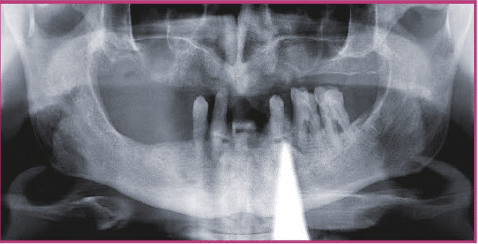

Nach entsprechender klinischer und röntgenologischer Diagnostik (Abb. 1a, b) wurden vier zweiteilige Keramikimplantate (Pure Ceramic, Straumann Group) für die Insertion im Oberkiefer Nach komplikationsloser dreimonatiger Osseointegration geplant (Abb. 2). Der Entscheidung bei der Auswahl dieser Medizinprodukte lag auch der Umstand zugrunde, dass die Implantate für systemimmanente Scanbodies kompatibel sind undüber sollte im digitalen Workflow hergestellt werden. Hierfür wurden zunächst die zum Implantatsystem passenden Scanbodies die sich schon bei der einteiligen Variante des Keramikimplantates (Monotype Pure Ceramic, Straumann Group) seitJahren auf dem Intraoralscanner (iTero, Align) digitalisiert (Abb. 5a).

Nach dem Import der STL-Daten in die CAD-Software (3Shape, Implantstudio) wurden die Abutments konstruiert. Da die Abutments zugleich die Funktion der Primärkronen einnehmen, ist auf ein entsprechendes Design geachtet worden. Aus Zirkonoxid gefräst sowie finalisiert wurden die Kronen im Partnerlabor CS-Zahntechnik. Danach erfolgte das Verkleben mit der Titanbasis, ein sensibler Vorgang. Insbesondere das Beseitigen der Kleberrückstände im basalen Bereich sollte unter dem Mikroskop erfolgen. Die Anschlussgeometrie des Abutments bleibt unangetastet. Weiterer Schlüssel für den Erfolg einer implantatprothetischen Restauration ist ein exaktes Modell und somit die präzise Umsetzung der digitalen Daten in ein physisches Modell. Das Modell wurde im Fertigungszentrum (iTero, Align) gefräst. Die CNC-gefertigten Implantatmodelle sind hochpräzise und haben sich im digitalen implantatprothetischen Workflow der Autoren zu einem festen Bestandteil etabliert. Zum Einsatz kommen speziell entwickelte Modellanaloge, die nachträglich in die hochpräzise Bohrung eingebracht werden.